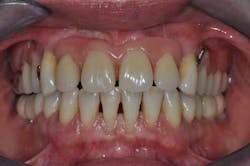

Fig. 2: Anterior teeth relationships prior to treatment